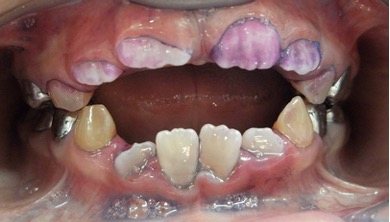

El examen clínico intraoral reveló alteración de la estructura y color de las piezas primarias, atrición y pérdida de la dimensión vertical (Figura 2). Radiográficamente se observó la presencia de coronas con marcada constricción cervical y raíces cortas (Figura 3). Presentaba alto riesgo cariogénico, por la presencia de lesiones de caries activas y dos restos radiculares, sumado a la anomalía estructural de la dentina (riesgo biológico específico) y bajo riesgo gingivoperiodontal. El riesgo socio-económico era alto por provenir de una familia con marcadas limitaciones económicas. Luego de la anamnesis, examen clínico y radiográfico, e interconsulta con el médico de cabecera se estableció el diagnóstico de DI Tipo I asociado a OI tipo I. Se planificó un tratamiento integral y preventivo con los objetivos de devolver forma y función, y proteger y evitar el desgaste de los tejidos conductas que pudieran interferir con el tratamiento.

Figura 2: Examen clínico intraoral del maxilar superior e inferior y vista anterior. Año 2007